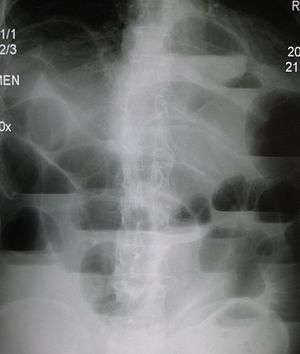

Radiological signs of bowel obstruction include bowel distension and the presence of multiple (more than six) gas-fluid levels on supine and erect abdominal radiographs.

Contrast enema or small bowel series or CT scan can be used to define the level of obstruction, whether the obstruction is partial or complete, and to help define the cause of the obstruction.

According to a meta-analysis of prospective studies by the Cochrane Collaboration, the appearance of water-soluble contrast in the cecum on an abdominal radiograph within 24 hours of oral administration predicts resolution of an adhesive small bowel obstruction with a pooled sensitivity of 96% and specificity of 96%.[11]